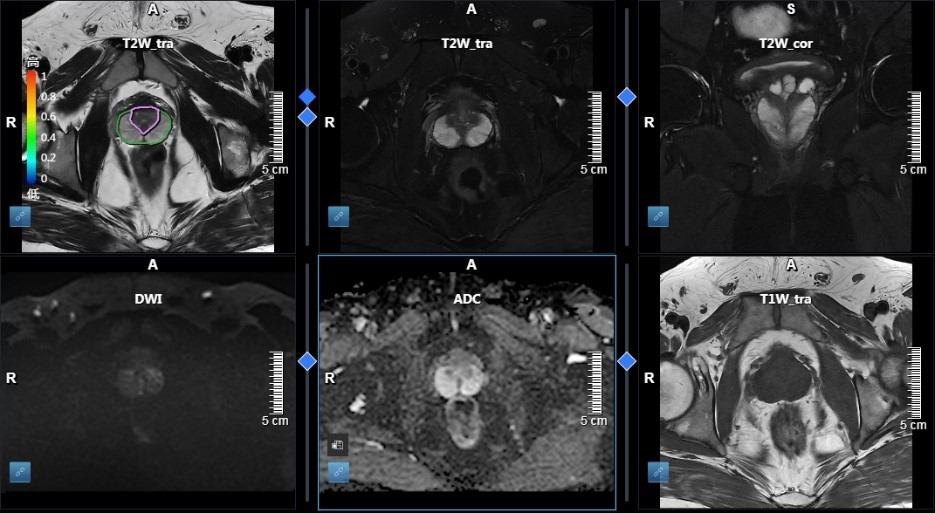

人工智能前列腺筛查技术